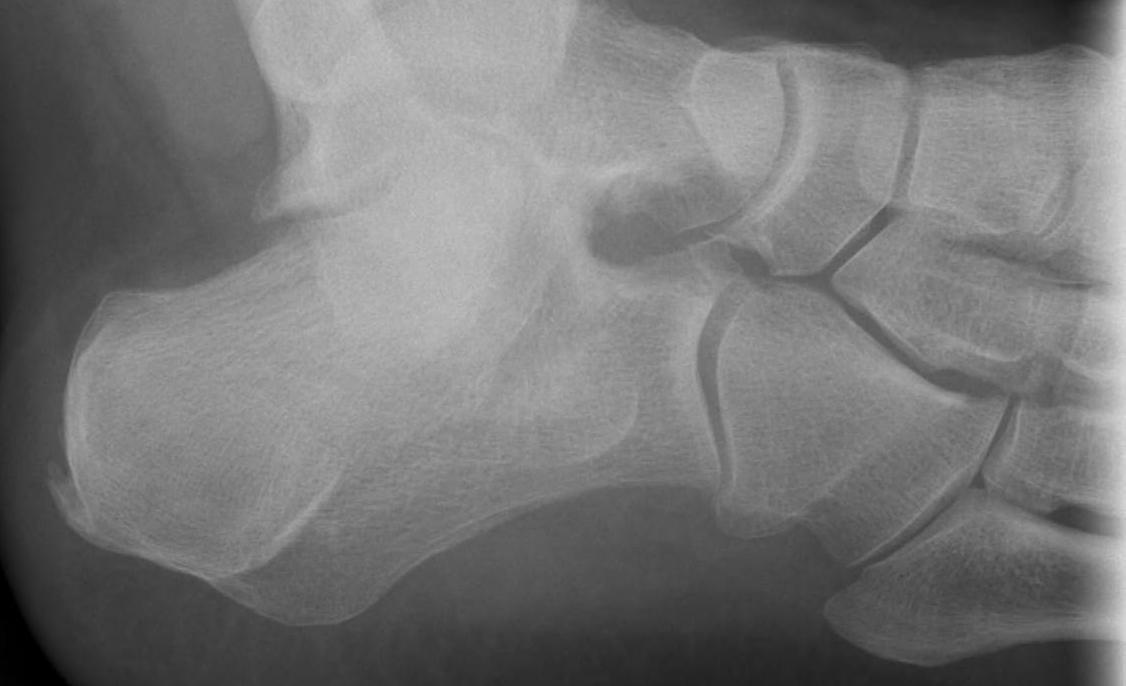

Fracture lateral process of talus